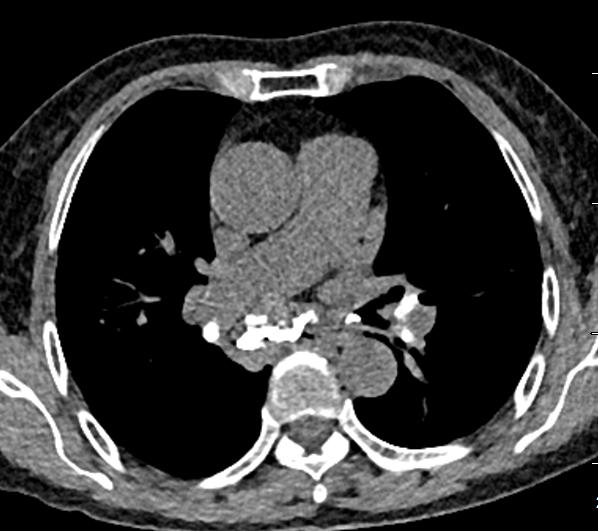

图10~图15 胸部CT示双肺多发钙化灶

问题出在哪儿?

右中间支气管的钙化病灶向外移动,钙化病灶的尖端刺激到支气管粘膜了(图16)。

图16 胸部CT

另外,这个患者的钙化灶非常危险,因为钙化灶的一端距离肺动脉才2毫米左右(图17),支气管镜下强行牵拉钙化病灶很可能会大出血危及生命。

图17 胸部CT